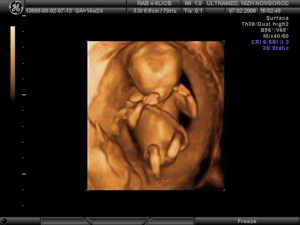

Именно в этот период происходит опущение яичек мальчиков в мошонку. В буквальном смысле малыш растет не по дням, а по часам, прибавляя более 1,0 г к своему весу. Если мама пропустит время приема пищи, он посасывает свой большой пальчик – это явление можно четко наблюдать на трехмерном (3D) или четырехмерном (4D) УЗИ 3 триместра.

Трехмерное УЗИ при беременности на поздних сроках дает возможность увидеть мельчайшие детали в развитии частей тела и органов ребенка. Высококачественное объемное изображение позволяет не только провести точную диагностику, но и сделать фотоснимки и видео внутриутробной жизни малыша.

С помощью 3D УЗИ возможно определить отклонения, которые порой не видны на обычном скрининге. Исследование является платным.

4D УЗИ, которое включает четыре измерения (ширина, высота, глубина и время), позволяет записать движения малыша в реальном времени. Диагност имеет возможность записать клип на диск и предоставить запись родителям. Конечно, эта услуга, как и сам скрининг, проводится платно.